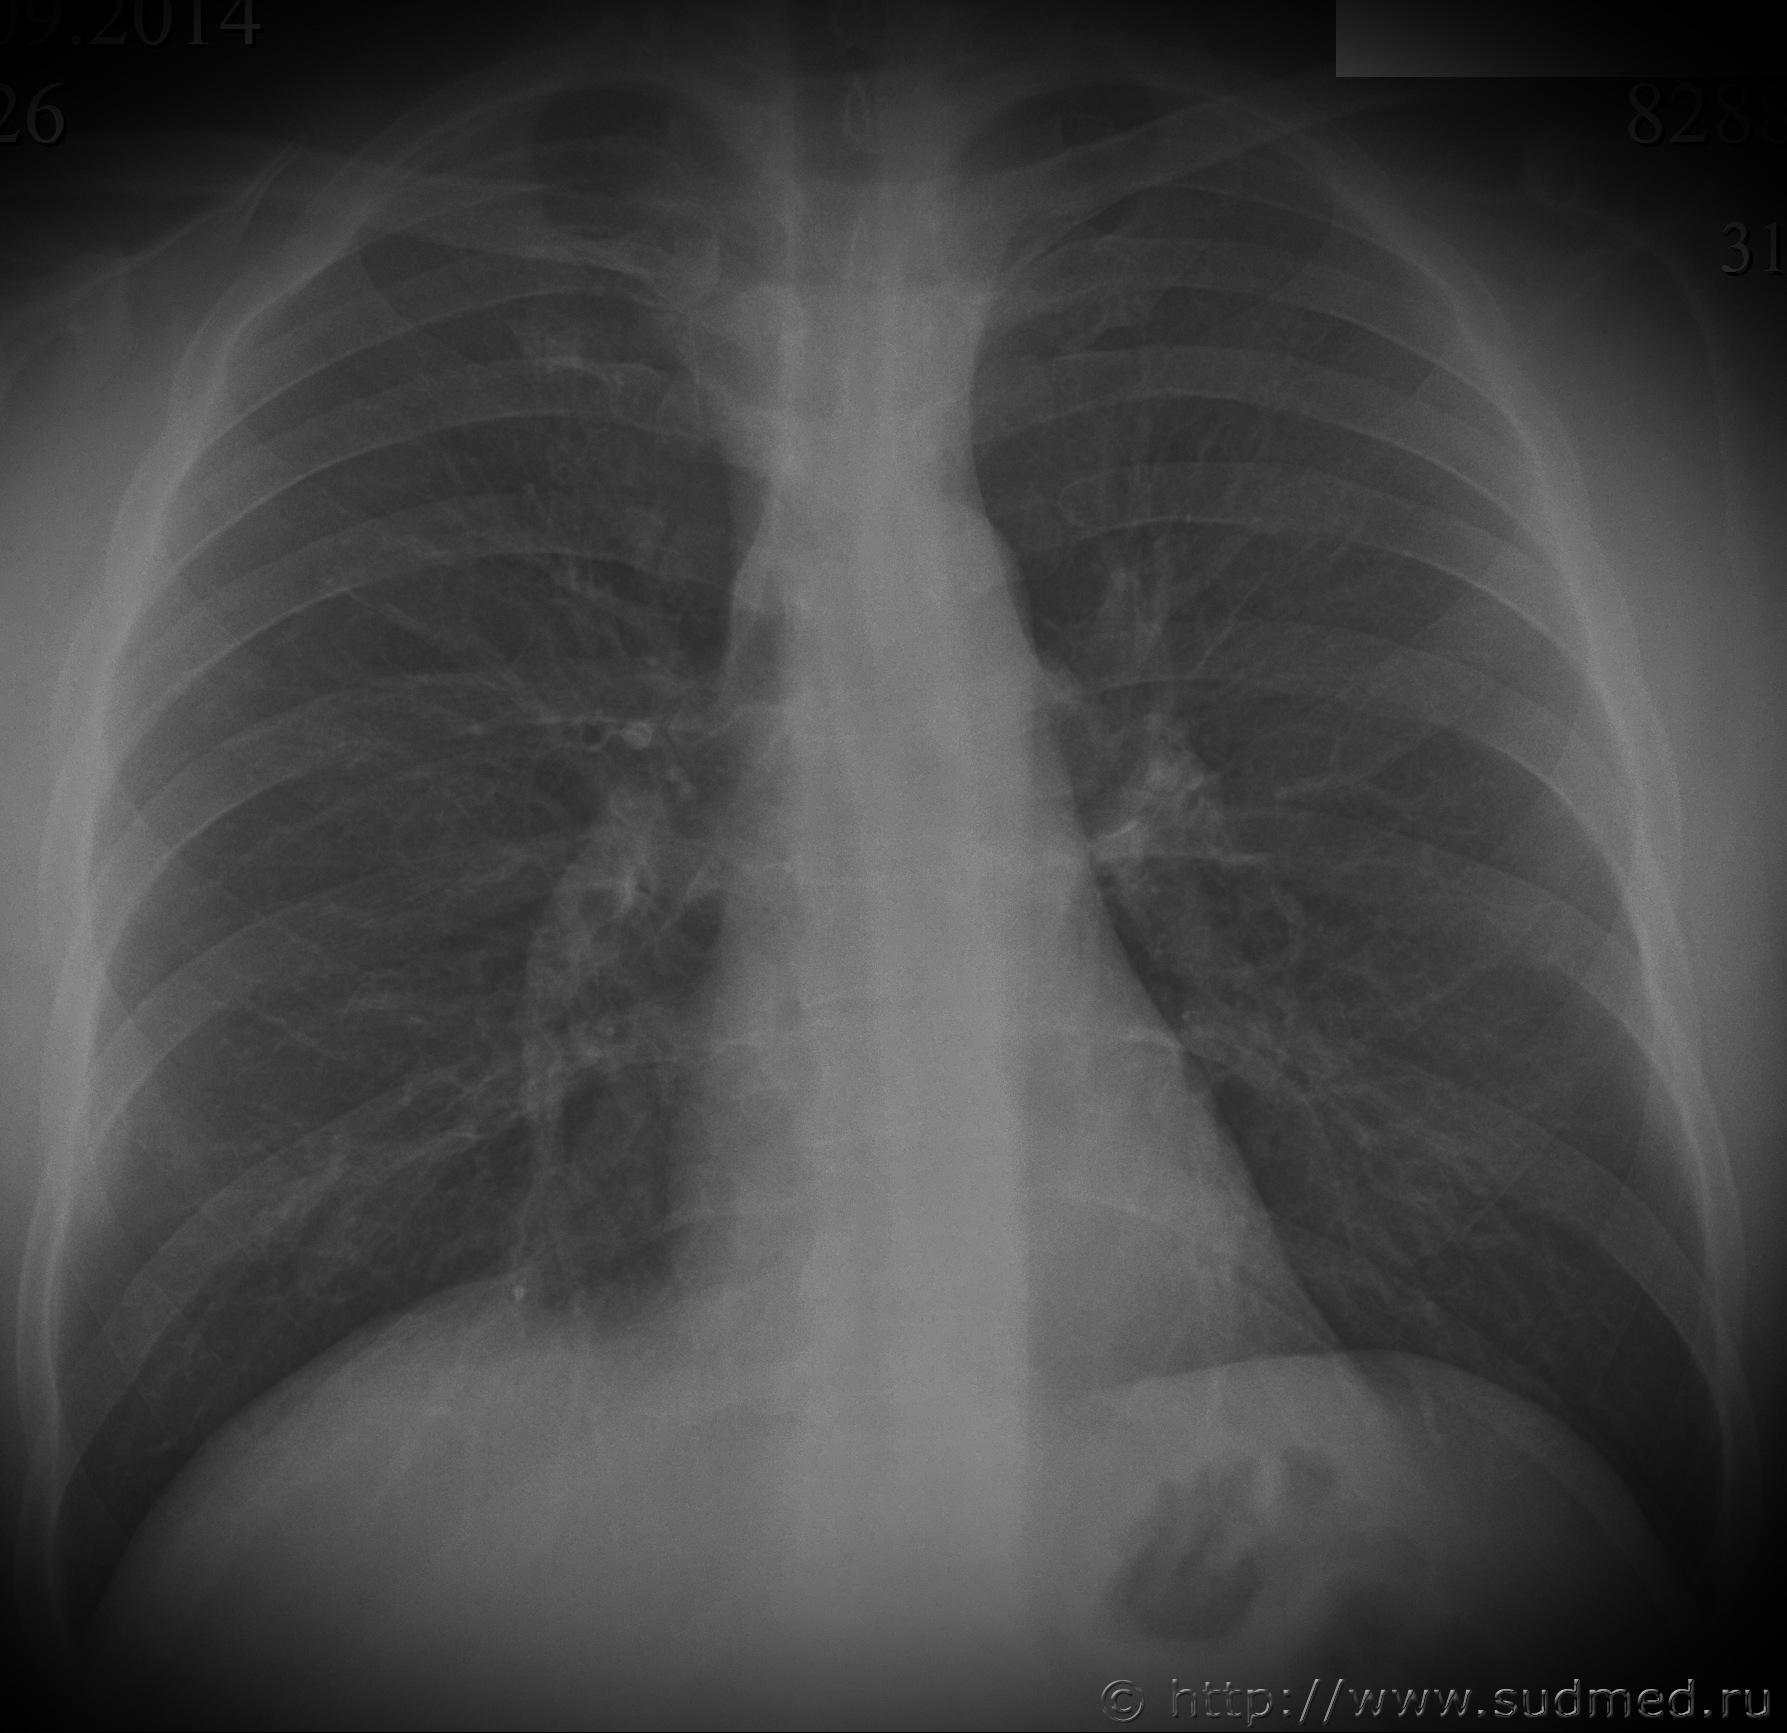

Некоторое время назад проводил экспертизу, у потерпевшего были переломы 8-10 ребер справа, ожидается что, может возникнуть вопрос по давности их образования, прикладываю предоставленные мне рентгеновские снимки. Какие мнения?

Изменений 8 и 10 ребер не вижу. Оч.похоже на посттравматическую деформацию (консолидированный перелом) 9 правого ребра между лопаточной и задней подмышечной линиями. Незначительная сглаженная "штыкообразная" деформация по верхнему и нижнему контурам ребра. Ступенеобразной деформации нет. Перерыва контура нет. Линия перелома не прослеживается. Костная структура восстановлена.

Если снимки сделаны на протяжении нескольких недель или более, то появляется еще один аргумент за давний перелом - отсутствие рентгенологических признаков динамики процесса (нет резорбции краев перелома и "расширения" его рентгенологической щели, нет появления и динамики костной мозоли).

Если же рентгенограммы сделаны относительно одномоментно (менее трех недель от даты предъявляемой травмы) и вопрос очень принципиален, то можно выполнить контрольные рентгенограммы: 1.правой половины грудной клетки в задней прямой проекции, 2.с выведением области интереса (вышеназванного изменения ребра) в краеобразующую зону. Тогда все станет еще более очевидно.

На 9-м ребре справа по задней подмышечной линии имеется участок деформации - но "свежих" переломов я не вижу... А так как на обоих снимках в прямой проекции этот участок в тени другого ребра (передних отделов) - я вообще не стал бы заморачиваться - написав об отсутствии "свежих" костно-травматических изменений.

Свежих переломов нет. Даже на счёт консолидированных - сомнительно, но полностью не исключаю (например, заживление перелома без смещения, либо не полного перелома). Как вариант, ходатайствовать копам о проведении КТ.